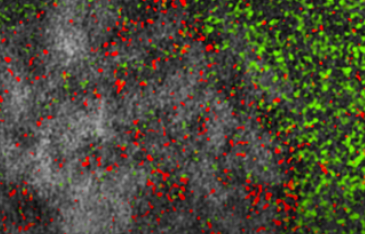

“在这里,我们研究了空间组织的β2-肾上腺素能受体(β2AR)信号如何控制ERK,”文章指出。“使用亚细胞靶向ERK活性生物传感器,我们表明β2AR信号转导在内体而非质膜处诱导ERK活性。”

“[内体]ERK活性池依赖于活性的、内体定位的Gαs,并且需要配体刺激的β2AR内吞作用,”该文章的作者继续说道。“我们进一步确定了一个包含Gαs、RAF和丝裂原活化蛋白激酶的内体定位的非经典信号轴,导致内体ERK活性传播到细胞核中。内体β2AR和Gαs信号的选择性抑制减弱了核ERK活性、MYC基因表达和细胞增殖。”